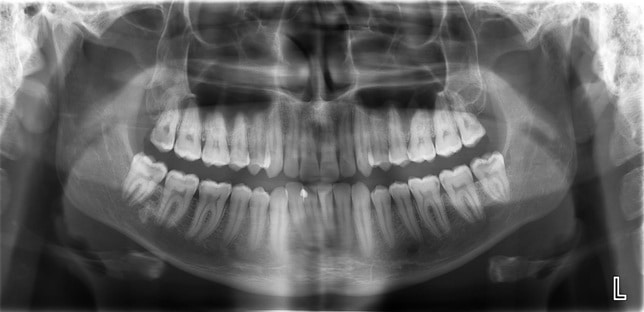

Đầu tiên khi đến với bệnh viện hoặc cơ sở nha khoa thì bạn sẽ được thăm khám kỹ lưỡng tình trạng răng miệng kết hợp với chụp X-quang để các bác sĩ nắm bắt được cấu trúc xương răng và lên phương án điều trị thích hợp nhất. Thông thường nếu như không phát hiện những cấu trúc phức tạp của răng và quá trình nhổ răng số 8 được thực hiện bằng cách: bác sĩ nha khoa tiến hành rạch một đường cắt trên nướu sao cho lộ chân răng bên dưới sau khi đã được tiêm tê và xịt tê tại chỗ, sau đó dùng kìm và các dụng cụ chuyên dụng để lấy răng ra khỏi xương hàm, cuối cùng là làm sạch, khâu vết thương (nếu có) và cầm máu bằng bông gạc.